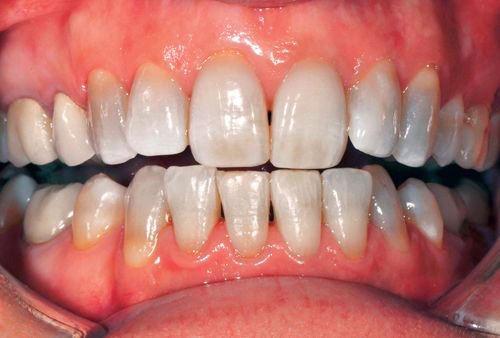

Các bác sĩ nha khoa đưa ra giải pháp hiệu quả cho bạn trong trường hợp thiếu sản men răng là phương pháp bọc răng sứ thẩm mỹ. Ngoài việc tạo nên một lớp bảo vệ bên ngoài cho răng, bọc răng sứ còn cải thiện được tốt nhất tình trạng răng bị nhiễm màu và các vệt lõm trên thân răng làm tăng thêm tính thẩm mỹ cho hàm răng của bạn.

Có nhiều khách hàng tìm đến Nha khoa Quốc tế Dencos Luxury với tình trạng răng bị đốm và đổi màu nghiêm trọng và được thực hiện dịch vụ bọc răng sứ thẩm mỹ. Họ cũng không khỏi ngạc nhiên vì vấn đề khiến họ tự ti, lo ngại bấy lâu lại được giải quyết nhanh và kết quả tốt đến thế.

Xin mời khách hàng tham khảo một số hình ảnh của phương pháp bọc răng sứ ngay dưới đây:

Kết quả bọc răng sứ khắc phục bệnh thiếu sản men răng

(Lưu ý: Kết quả tùy thuộc cơ địa mỗi người)

Khắc phục thiếu sản men răng bằng phương pháp bọc răng sứ thẩm mỹ là giải pháp vẹn toàn để ngăn chặn được những tác động bên ngoài gây hại men răng. Tránh cho răng càng ngày càng tổn thương và mang lại tính thẩm mỹ tốt nhất.